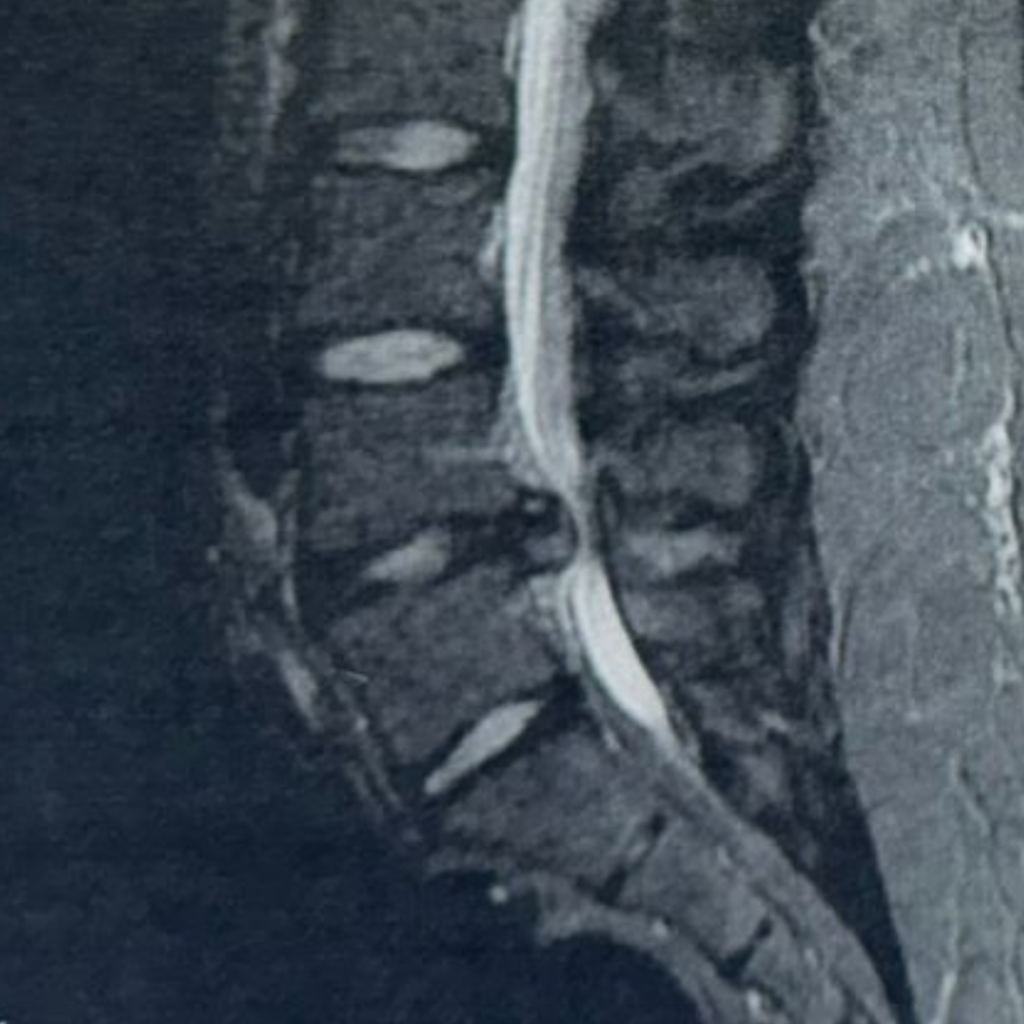

Back pain is common—but when pain shoots down the leg, cripples mobility, and refuses to improve despite weeks of treatment,